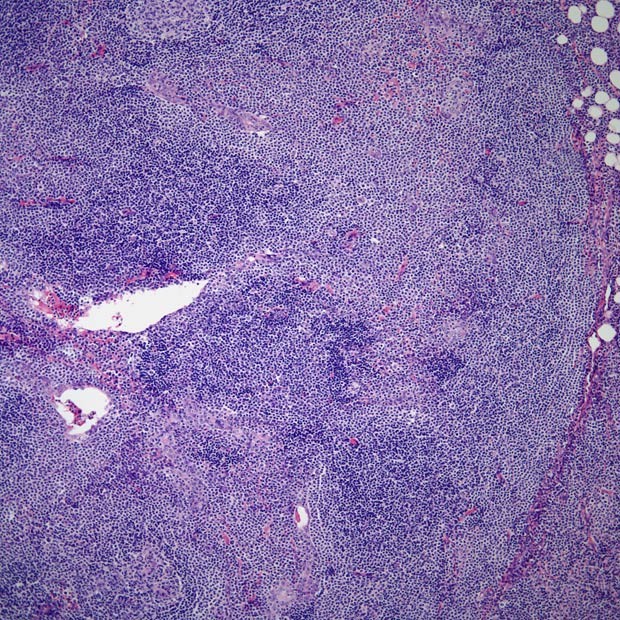

图23 黏膜相关淋巴组织(malt)淋巴瘤单核细胞增殖

8例肠黏膜相关淋巴组织淋巴瘤的临床病理特征

降结肠环形黏膜隆起镜下这么多淋巴细胞是单纯炎症可能吗?